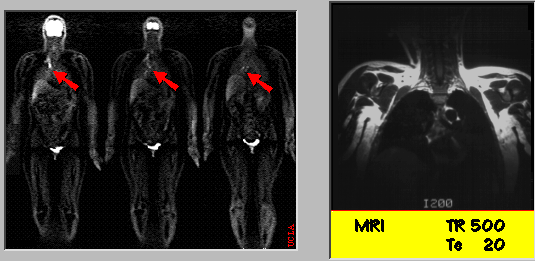

FDG-PET and MRI

Right supraclavicular fine-needle aspiration revealed metastatic adenocarcinoma. The needle aspiration was based on the FDG-PET whole-body scan, which shows increased FDG metabolism along right paraspinal region extending up to right lower cervical area highly suspicious for metastatic breast carcinoma. Note that the MRI is negative.